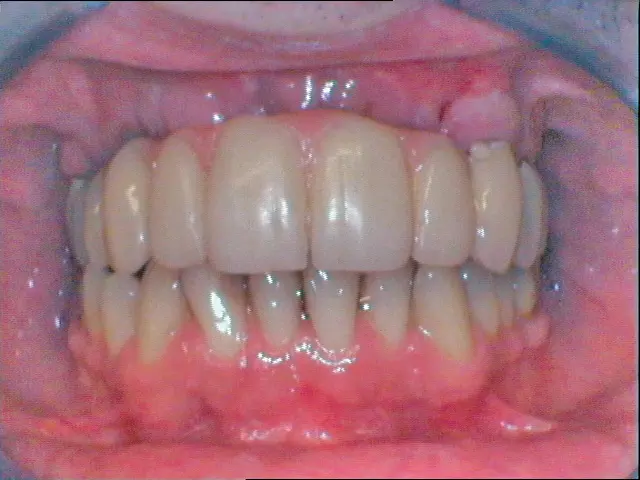

Nach Freilegung der Implantate regio 026,027 im Februar 2020, bei der auch die Implantation regio 037 (T3, Zimmer Biomet Dental, 4,0 mm x 13,0 mm) vorgenommen wurde (Abb. 32 OPG nach Freilegung), erfolgte im März nach Abformung mit offenem Löffel (open tray technique) und Gesichtsbogenregistrat die prothetische Versorgung mittels CAD/CAM gefräster Abutments (Dentaltechnik Hessel und Lutgen, Trier) und transversal verschraubter, verblockter VMK-Kronen (Abb. 33-36). Die Freilegung und Versorgung des Implantates 037 ist zusammen mit der Entfernung des Zahnes 38 für Juli 2020 geplant.